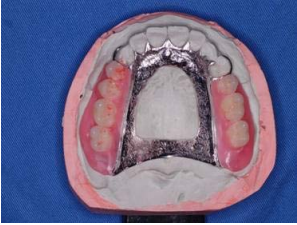

42. 下列附圖所顯示之狀況,何者錯誤?

(A)不宜採用馬蹄型連接體(horseshoe connector) (B)採用修正模型步驟(corrected cast procedure)灌製出之主模型 (C)亦可採用全覆蓋式(complete palate)主連接體 (D)此為甘迺迪分類(Kennedy classification)第一類型